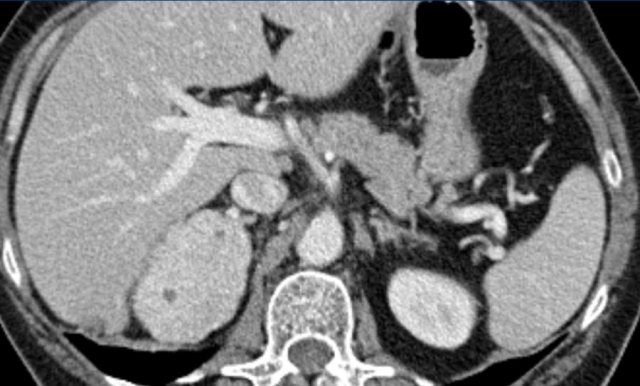

Axial venous phase CT in mediastinal and bone window setting Axial venous phase CT in mediastinal and bone window setting

Images depict mediastinal and bone window setting of a patient with a bulky heterogeneously enhancing right adrenal tumor.

This was proven to be an adrenocortical carcinoma.

There is a faint, ill-defined liver lesion in segment 6 and there are non-specific sclerotic changes in the body of T12.

Continue with the PET-image...

PET-CT performed for complete staging shows intense uptake in the adrenal tumor, indicative of its malignant nature.

There is also intense uptake in two liver metastases and in a bone metastasis in T12.

Approximately 20-40% of patients with an adrenocortical carcinoma present with metastases at diagnosis.